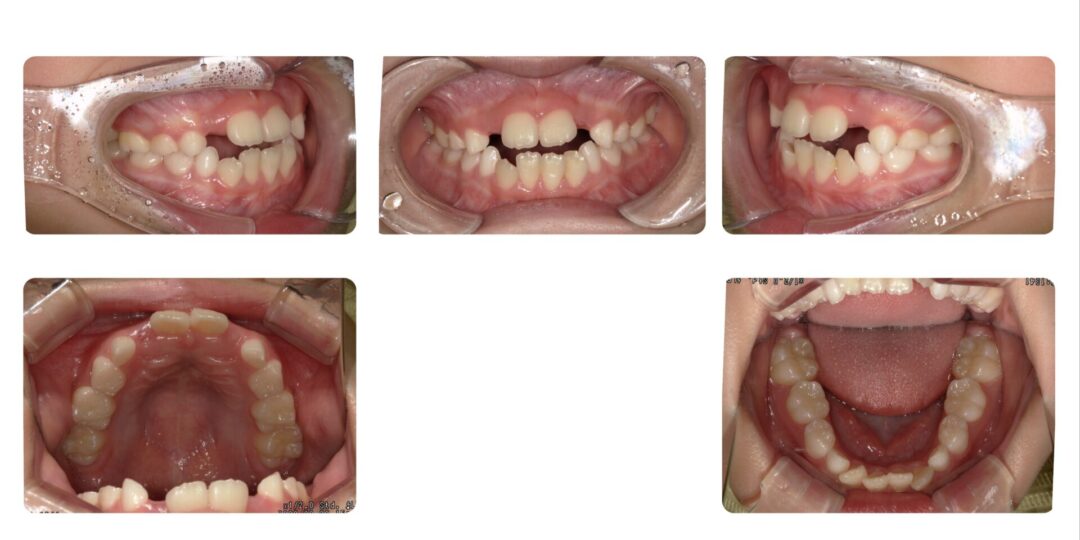

矯正治療前

初診時7歳

第一期治療 上下拡大床(上顎タングガード付)

2年8ヶ月

自由診療 基本料金¥330,000 処置料¥3,300